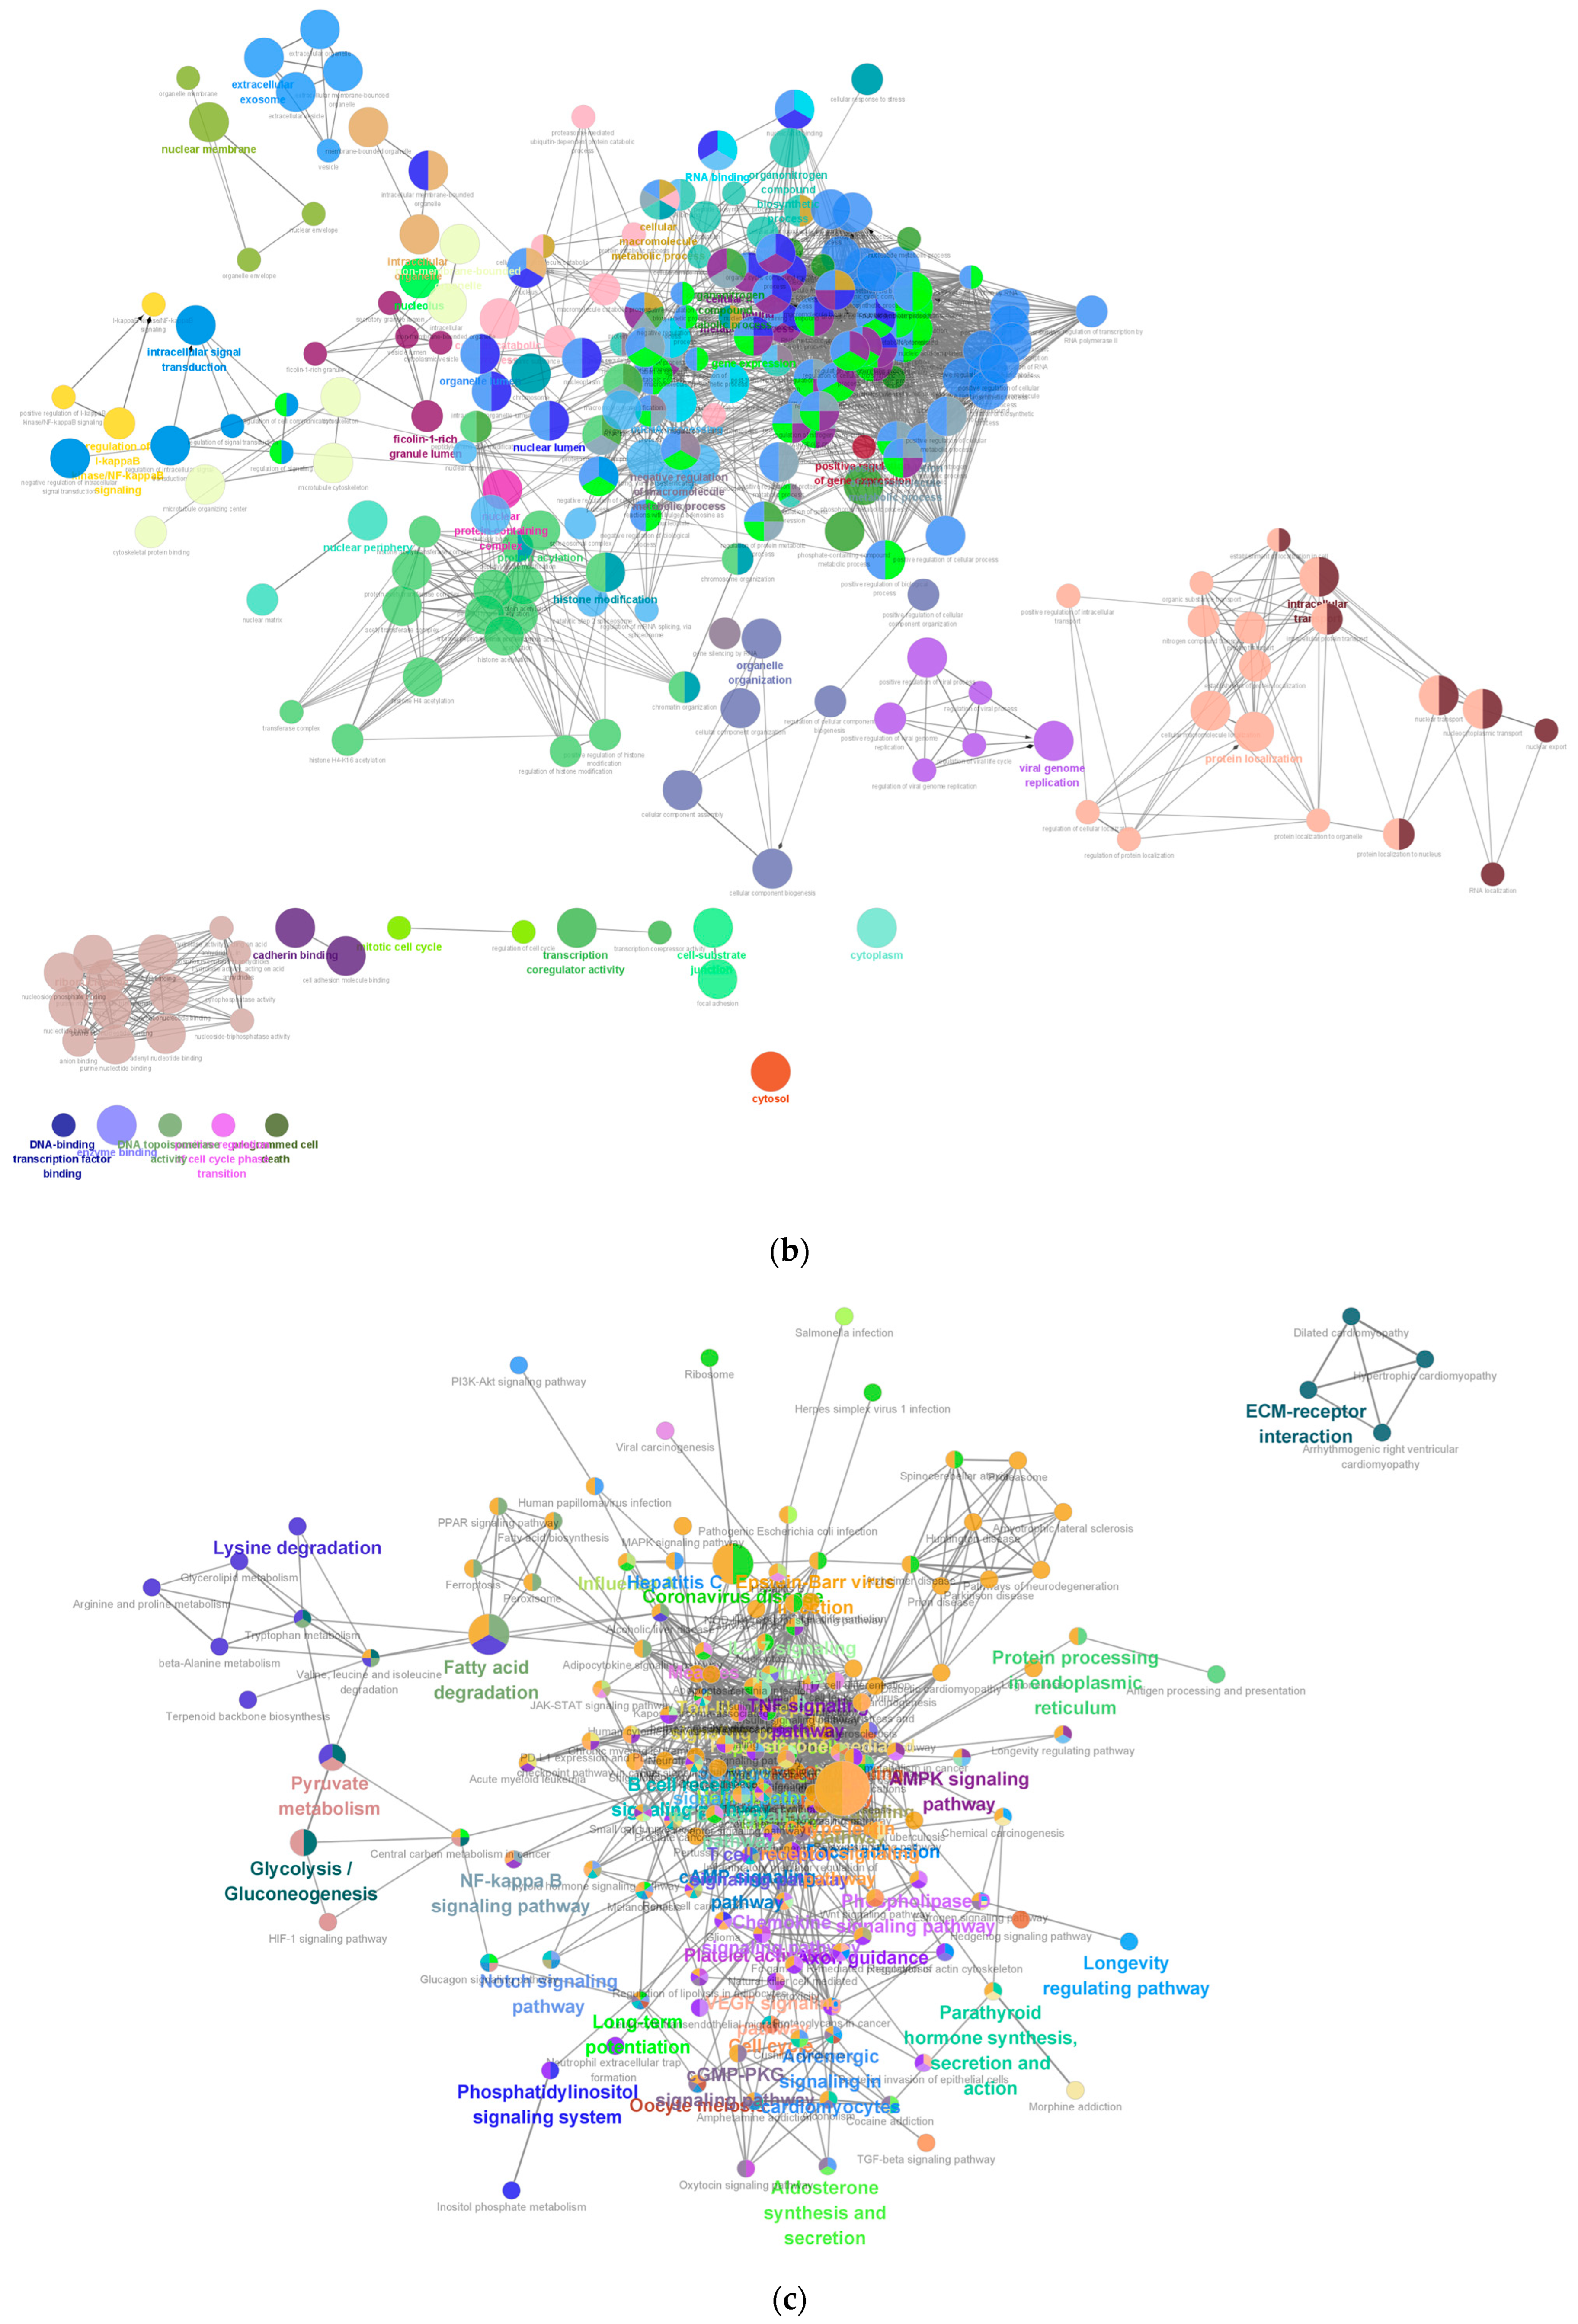

2.7. Functional Enrichment Analyses of Hub Genes

Functional enrichment analysis including GO and KEGG were performed to identify which DEGs were significantly enriched in GO terms and which metabolic pathways had a Bonferroni-corrected p-value ≤ 0.05 compared with the whole-transcriptome background. GO functional enrichment and KEGG pathway analysis were carried out by Goatools (version 0.12.1) and Python scipy (version 1.10.1) software, respectively.

Enrichment analyses, grouped by functional categories (

Table 3), revealed a predominance of RNA processing and immune response pathways consistent with

C. acnes-induced inflammation. These analyses further identified the C-type lectin receptor (CLR) signaling pathway as a key mediator of

C. acnes IA

1–induced inflammation. CLRs, expressed on keratinocytes and immune cells, recognize bacterial glycans, activating NF-κB and MAPK pathways to drive cytokine production [

25]. Our KEGG results, which also enriched NF-κB signaling, suggest a synergistic mechanism where

C. acnes IA

1 exploits CLR-mediated recognition to amplify inflammatory cascades, contributing to the chronicity of acne lesions [

26]. Additionally, enrichment of interferon-mediated signaling and Notch signaling indicates broader immune modulation, with interferons enhancing antiviral-like responses against bacterial PAMPs and Notch regulating epidermal differentiation [

27]. Reactome and Disease Ontology (DO) analyses further linked DEGs to chromatin modification and dermatological conditions, reinforcing acne’s inflammatory nature akin to psoriasis or eczema [

28].